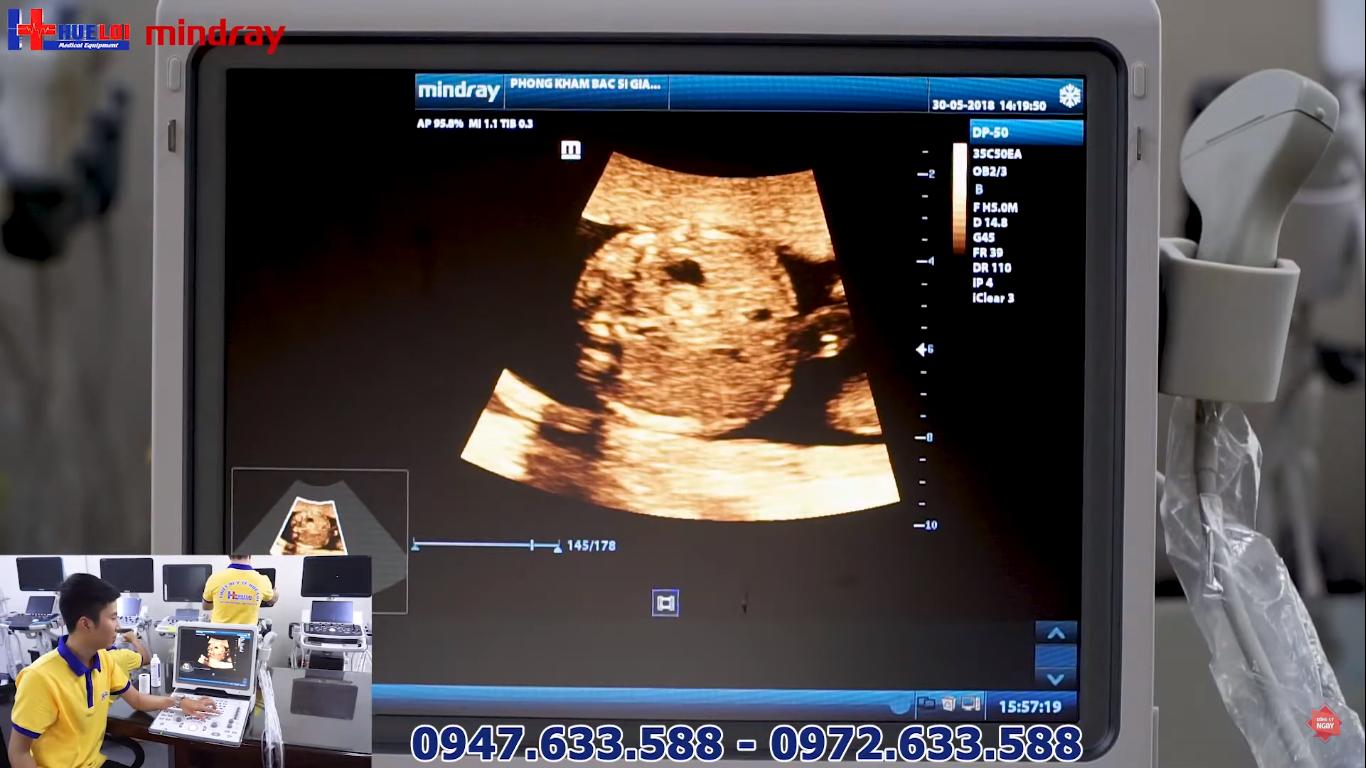

Máy siêu âm xách tay Mindray DP 50 với mức giá chỉ dưới 200 triệu trên 2 đầu dò, Mindray DP 50 được cải tiến rõ rệt về thiết kế và đặc biệt là chất lượng hình ảnh.

Màn hình LED 15”, độ phân giải cao 1024 x 768, điều chỉnh được góc nghiêng 30 độ

2D ổ bụng - Đầu dò Convex

- Ưu điểm: Tích hợp thêm chế độ Doppler Xung cùng với Phần mềm tự động đo đạc trong chế độ Doppler Xung. Thiết kế nhỏ gọn, hình ảnh được cải thiện rõ nét giúp các Bác Sỹ giảm thời gian chẩn đoán mà vẫn tiết kiệm ngân sách

- Nhược điểm: Chất lượng hình ảnh của Mindray DP 50 chưa thực sự hoàn hảo. Nhưng nếu so với mức giá chỉ dưới 200 triệu thì DP 50 lại rất đáng để cân nhắc đầu tư cho các Bác Sỹ